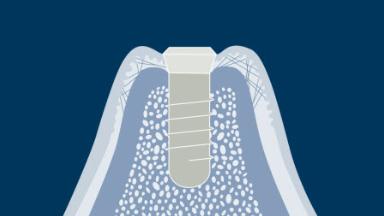

Integration into bone is called osseointegration and this phenomenon essentially revolutionized how missing teeth can be replaced.

Osseointegration has implications for all dentists as well as for patients with any missing teeth. Implants are anchored in bone tissue and penetrate the soft tissue.

It is essential to understand the soft and hard tissues around dental implant restorations since only this allows for optimal restorations.